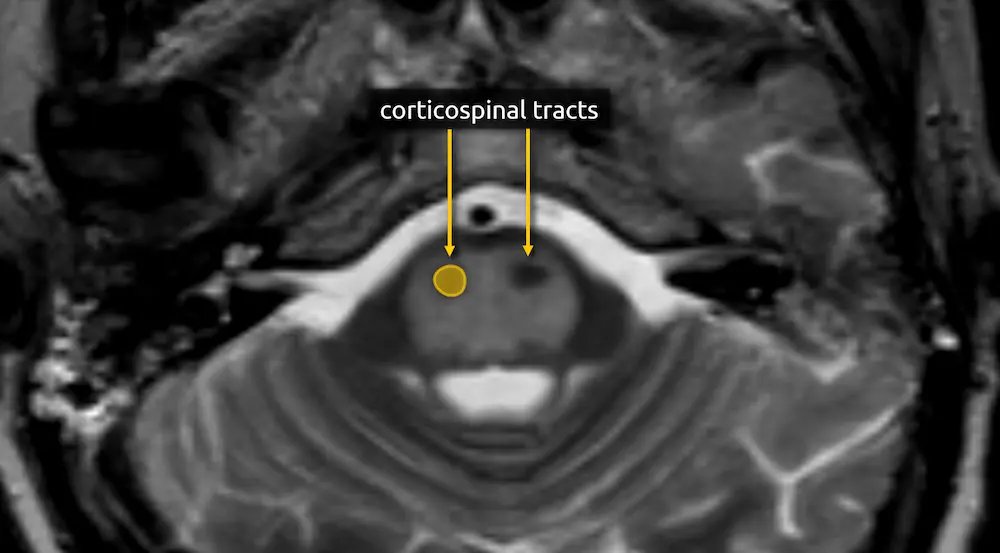

3. Corticospinal tracts

The corticospinal, corticobulbar, and corticopontocerebellar tracts continue inferiorly from the cerebral peduncles.

Lesions of the corticospinal tracts will cause motor deficits of the body and limbs. Sparing or involvement of the corticospinal tracts is a characteristic finding of several conditions, e.g., sparing of the corticospinal tracts is responsible for the "trident sign" of osmotic demyelination syndrome. The corticobulbar tract is located along the medial aspect and can be selectively damaged at this level, producing facial weakness.

1. Corticospinal tracts